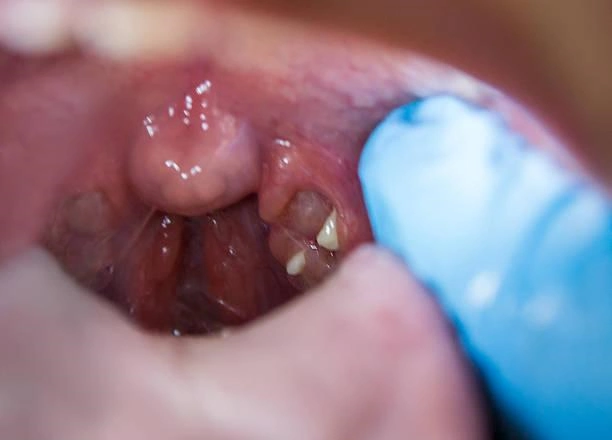

A cirurgia de amígdalas com plano de saúde é um procedimento cirúrgico realizado para a remoção das amígdalas, que são órgãos linfoides localizados na parte de trás da garganta.

As amígdalas podem causar diversos problemas de saúde, como infecções frequentes, dores de garganta recorrentes, dificuldade para engolir e até mesmo apneia do sono.